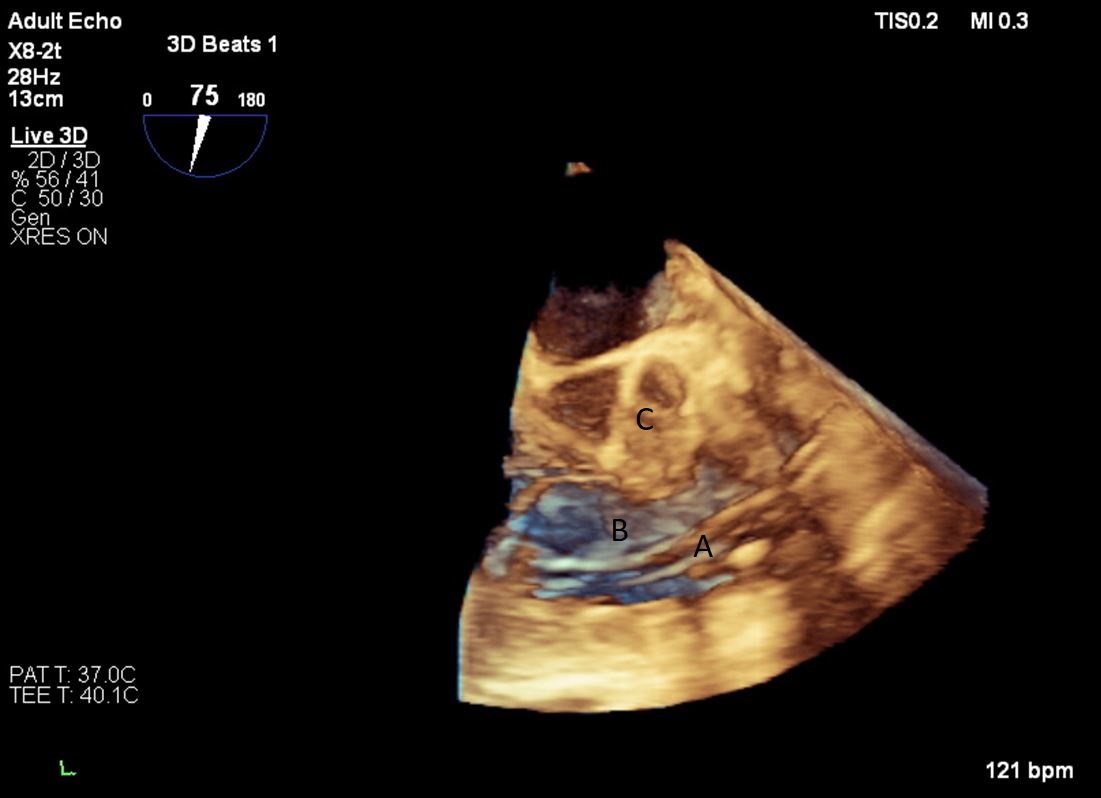

Both TTE and TEE can help with ideal positioning of the Impella (Figs. 5,6). The distance from the aortic valve to the Impella inlet should be measured. This should ideally be 3.5–4 cm for all Impella devices except for the Impella 5.5 for which it is 5 cm [15] (Fig. 7). The outlet should be 1.5–2 cm above the sinuses of Valsalva. The catheter should be angled towards the LV apex and away from the septum and mitral valve. The positioning of both the inlet in the LV cavity and the outlet above the aortic valve should be confirmed. Color flow doppler imaging can help confirm this positioning as a mosaic pattern will be visualized near the inlet and outlet ports on spectral doppler (Fig. 8). Real-time 3D echocardiography can also be used to help in visualizing Impella positioning relative to other anatomical structures (Fig. 9). After placement of the Impella, the aortic and mitral valves should be interrogated for any new or worsening regurgitation or dysfunction [16]. TEE can also help identify additional complications of Impella placement including pericardial effusion or LV free wall rupture [17].

Fig. 9.Real time 3D TEE imaging visualizing the Impella in relation to the aortic valve and LVOT. (A) Impella. (B) Ascending aortic root.